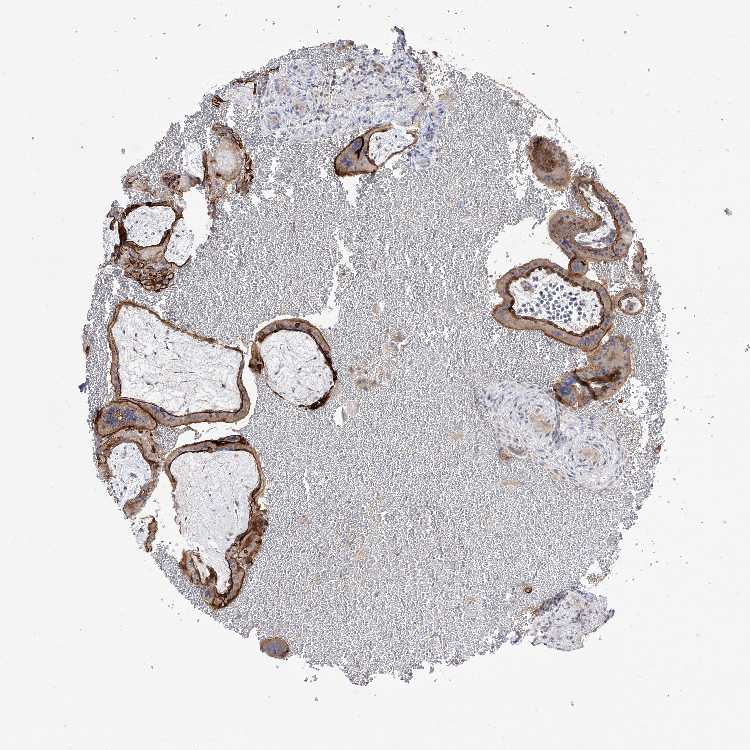

Antibody staining in the annotated cell types in the current human tissue is reported as not detected, low, medium, or high. This score is based on the staining intensity and fraction of stained cells.

Information about each individual sample is listed below, including gender, age, a tissue section image and estimated fractions of cell types. pTPM (transcripts per million) values give a quantification of the gene abundance which is comparable between different genes and samples.